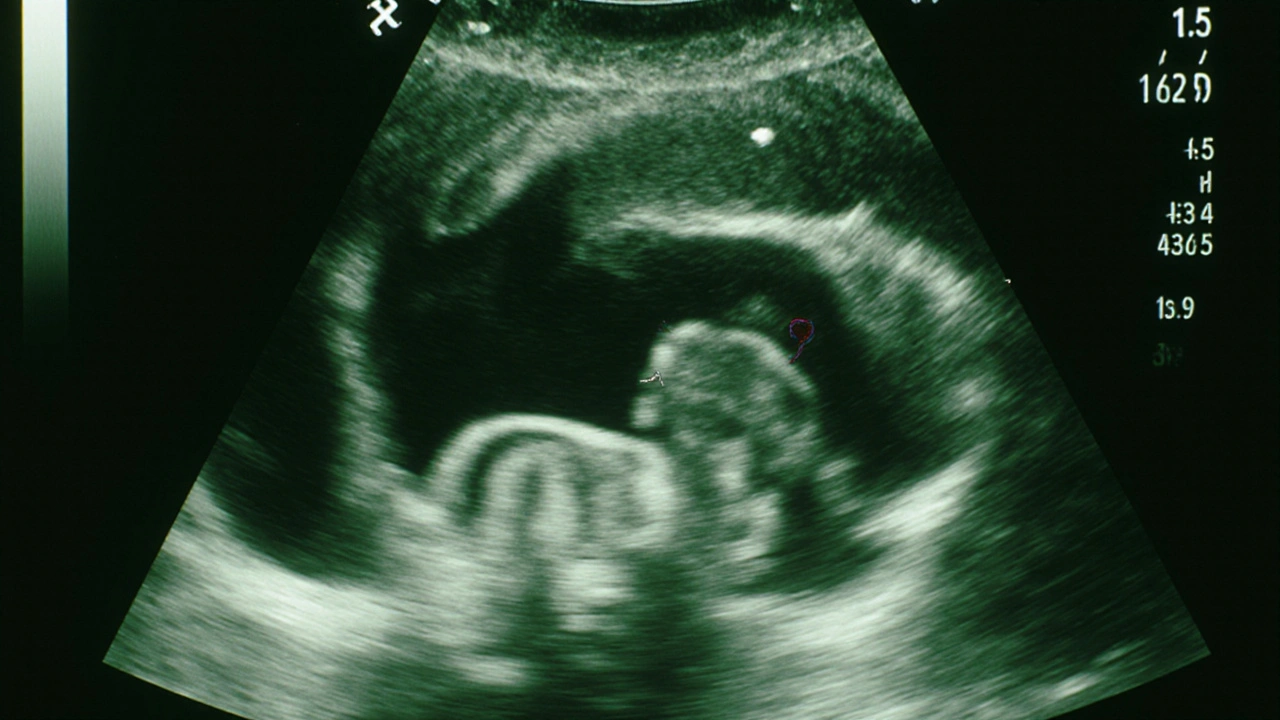

V 7. týdnu už je srdce plodu jasně vidět. Jeho tep je obvykle mezi 100 a 160 úderů za minutu. To je rychlejší než tvoje vlastní tep - a to je normální. Tělo plodu je ještě malé, ale už se začínají formovat základy rukou, nohou a hlavy. Na snímku můžeš vidět malý výběžek, který je začátek paží, a kousek, který bude v budoucnu hlavou.

V 8. týdnu se začíná objevovat pohyb. Nejde o skutečné pohyby, jak je známe později, ale o drobné trhnutí, které vzniká kvůli vývoji nervového systému. Některé přístroje už dokážou zachytit tyto pohyby. Tělo plodu je teď asi 1,5 cm dlouhé - velikost hrášku. I když to zní malé, už má všechny základní orgány - jen jsou ještě v rané fázi vývoje.

Malý plod o velikosti hrášku na ultrazvuku s viditelnými výběžky končetin a bijícím srdcem.